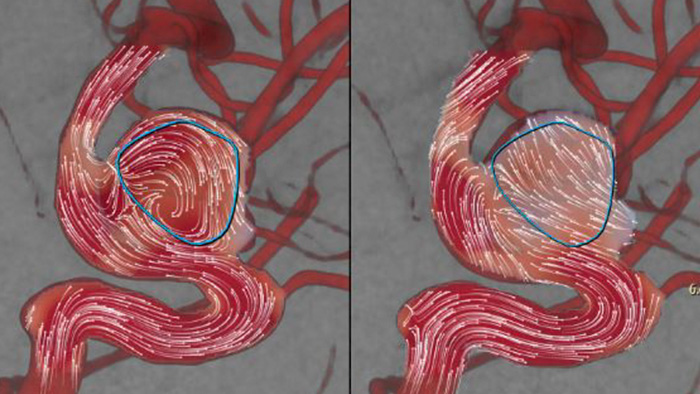

AneurysmFlow está diseñado para ofrecerle información relevante antes y después de la implementación del desviador de flujo. Visualiza y cuantifica los cambios en el flujo para aumentar la confianza en la eficacia del procedimiento.